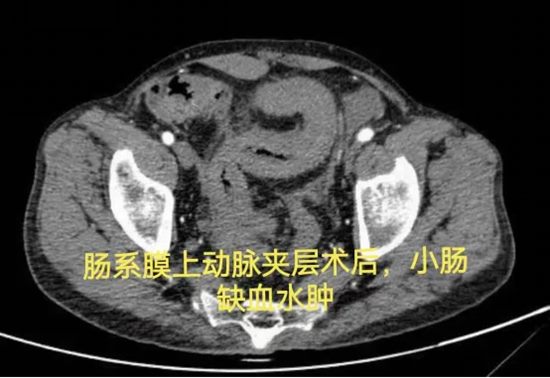

病例六:支架术后肠瘘,历经三次手术未愈,为何选择“等待”

病情简述:53岁男性,肠系膜上动脉夹层术后出现复杂肠瘘,经历三次手术仍无法愈合,入院时白蛋白仅15.0g/L(严重营养不良)。

诊疗破局:面对再次手术的高风险,团队决定“先退一步”,将治疗重点转向营养支持。经过长达3个月的肠内联合静脉营养强化治疗,待患者身体状况改善后,再成功施行“腹腔镜肠粘连松解、瘘口小肠切除+远端回肠及回盲部结肠切除术”,最终成功康复。

技术体现:有时候,充分的术前准备与对手术时机的精准把握,比手术本身更重要。